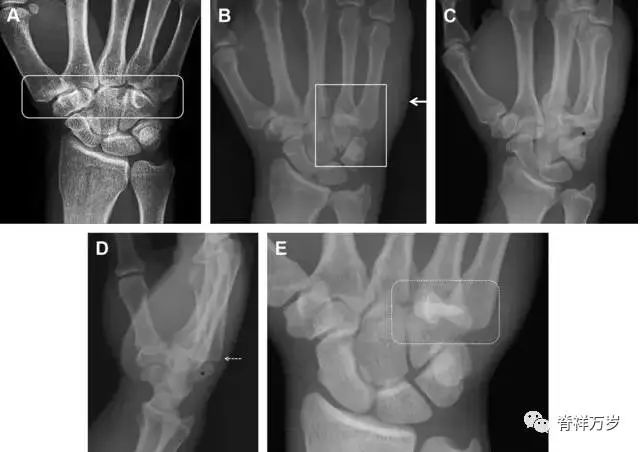

32.掌板骨折

掌板是掌指关节和指间关节关节囊掌侧的纤维结构,防止关节过伸。掌板的远端部是增厚的纤维软骨,附着于指骨掌侧基底部,而其两侧与侧副韧带的纤维融合。掌板骨折多发生于过伸损伤,为撕脱性骨折。

图 3 掌板骨折(A~C)小指前后位、斜位、侧位片,由于骨折的部位及特点,在前后位片上通常难以发现骨折;放大后的斜位(D)、侧位(E)可见一骨碎片(白色箭头)。

33.腕掌关节骨折脱位

腕掌关节骨折脱位为高能量损伤,常伴有神经损伤。腕掌关节组成骨多,侧位片上重叠遮挡多,骨折不易发现,容易漏诊。在前后位片上,关节面不平滑、关节间隙不对称、关节皮质破坏、关节面重叠常提示腕掌关节骨折脱位。特别是第 4、5 腕掌关节脱位,在前后位片上不容易发现;该损伤不稳定,也称为「变异型拳击手损伤/骨折」。

图 4 第 4、5 腕掌关节骨折脱位。(A)正常腕掌关节,关节面平衡起伏、平行;前后位(B)、斜位(C)、侧位(D),第 5 掌骨近端附近软组织肿胀(白色箭头),冠状面关节面重叠,背侧撞击剪切应力致钩状骨骨折(*),在前后位及斜位片上可见双密度影。第 4 掌骨底部可见微小骨折碎片(D,虚线箭头),第 4、5 掌骨掌侧成角。(E~G)变异型拳击手损伤:第 4、5 掌骨背侧脱位而未见骨折(E,虚线方框),钩状骨有骨折小碎片(F,短虚线箭头),第 4 掌骨基底部关节内骨折(G,长虚线箭头)。